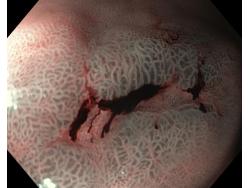

Krwawienie